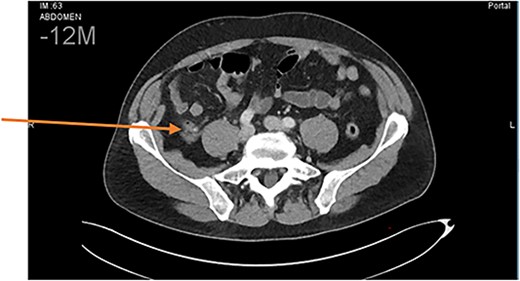

Abdominal computed tomography findings were compatible with uncomplicated acute appendicitis (Fig. 1).

Abdominal CT scan. Diagnosis of uncomplicated acute appendicitis.